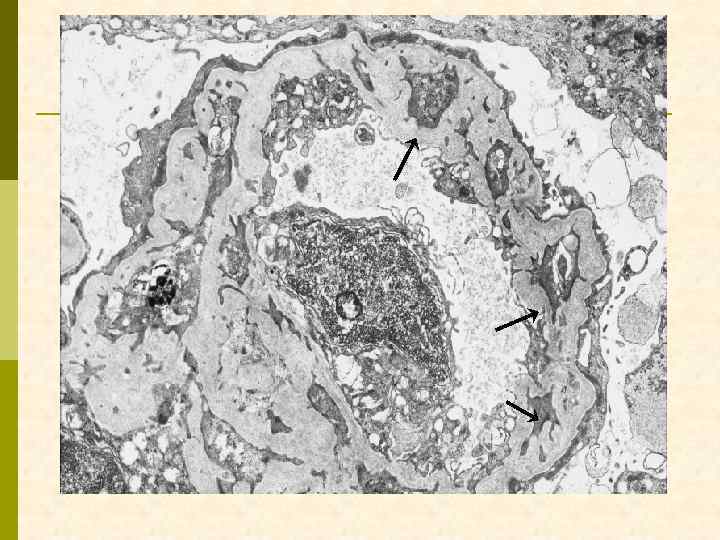

«микротромбы» (фибрин + тромбоциты)

множественные криоглобулин-содержащие интралюминальные депози